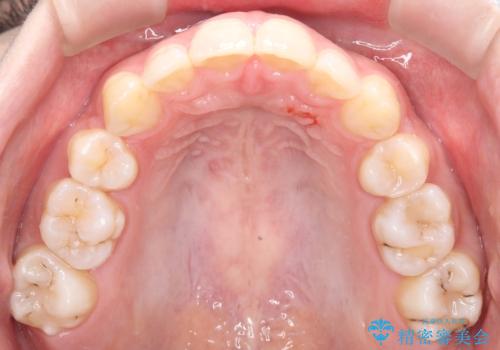

- 前歯から奥歯にかけて歯の重なりが激しい歯のがたつき(重度叢生)を主訴にご来院されました。精密検査の結果、歯が並ぶスペースが大幅に不足しており、歯並びを整え、口元を美しく引っ込めるためには、スペースの確保が必要と診断しました。そこで、上下左右の第一小臼歯(4番目の歯)を計4本抜歯し、そのスペースを利用して歯並び全体を整える抜歯矯正の治療計画を立案。装置には、透明で目立たないインビザラインを採用し、審美性と治療効果の両立を目指しました。

今回の治療では、重度の叢生を改善するため、まず計画通り上下左右4本の小臼歯を抜歯し、歯を並べるための十分なスペースを確保しました。装置には透明で取り外し可能なインビザラインを使用。抜歯によってできたスペースを最大限に活用し、マウスピースを定期的に交換しながら、デコボコを解消しつつ、前歯を効果的に後退させました。

治療の結果、長年の悩みであった重度の歯のがたつきが解消され、口元の突出感も改善。機能的にも安定し、審美的にも美しい、理想的な歯並びを獲得していただけました。